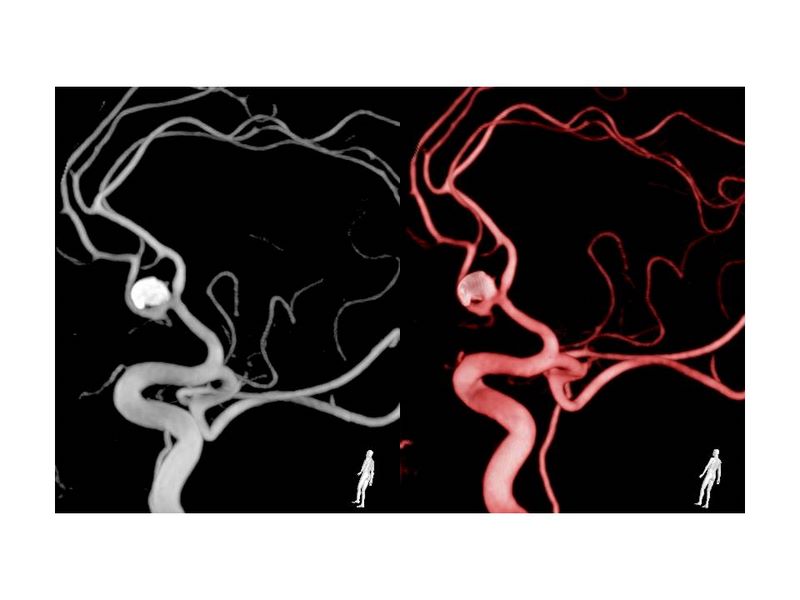

Aneurismas